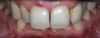

Prévisualisation du futur sourire

Prévisualisation du futur sourire. Cas clinique 4 : simulation de pose de facettes céramiques sur les incisives latérales.

Le sourire est naturel et plus présent Les diastèmes sont refermés par 2 facettes céramique sur les incisives latérales et une stratification de composite sur la canine gauche

Le sourire est naturel et plus présent, diastèmes refermés par 2 facettes et composite. Cas clinique 4 : facettes latérales.